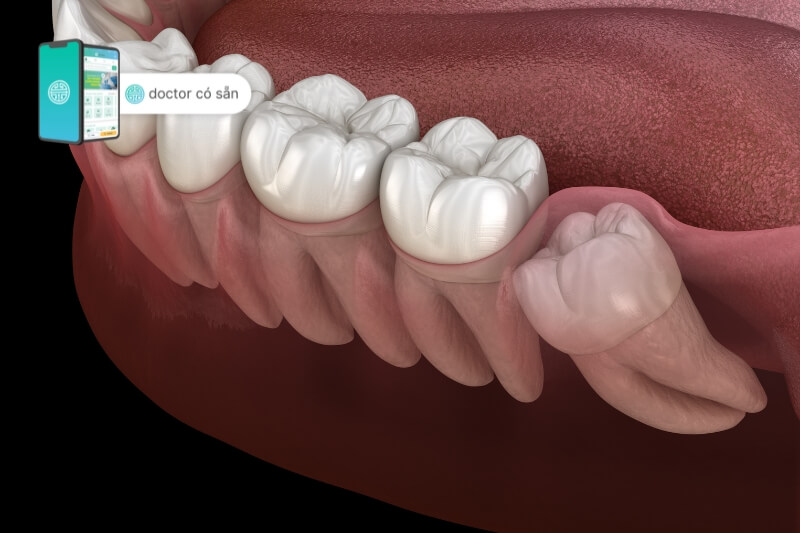

Ở những người có sự phát triển của răng khôn, việc nhổ răng khôn bị viêm nướu là tình trạng thường xuyên gặp. Bệnh viêm nướu răng khôn khi một phần của lợi ở hàm che phủ lên bề mặt của răng này, tạo ra môi trường không thuận lợi cho sự phát triển của nó. Khi răng khôn tiếp tục nảy mọc, nó sẽ chạm vào mô nướu, dẫn đến cảm giác đau và không thoải mái.

- Vị trí và cách răng khôn mọc: Nếu răng khôn mọc không đúng vị trí hoặc có góc mọc bất thường, nó có thể tạo ra sự cản trở với nướu xung quanh, gây viêm và sưng.

- Ảnh hưởng đến các răng lân cận: Mọi bất thường ở răng khôn đều có thể ảnh hưởng đến sức khỏe của các răng lân cận. Sự mọc lệch và tình trạng viêm nhiễm có thể gây tổn thương cho các chân răng xung quanh, đặc biệt là tạo điều kiện cho sự lệch và lung lay, khiến răng dần trở nên yếu đi.